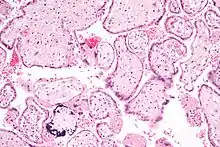

HCMV is one of the vertically transmitted infections that lead to congenital abnormalities. (Others are: Toxoplasmosis, Rubella, and Herpes simplex.) Congenital HCMV infection occurs when the mother has a primary infection during pregnancy.[29][30][31]

Up to 5 of every 1,000 live births are infected. Five percent develop multiple handicaps, and develop cytomegalic inclusion disease with nonspecific signs that resemble rubella. Another five percent later develop cerebral calcification (decreasing IQ levels dramatically and causing sensorineural deafness and psychomotor retardation).

CMV infection can be demonstrated microscopically by the detection of intranuclear inclusion bodies. On H&E staining, the inclusion bodies stain dark pink and are called "owl's eye" inclusion bodies.[45]